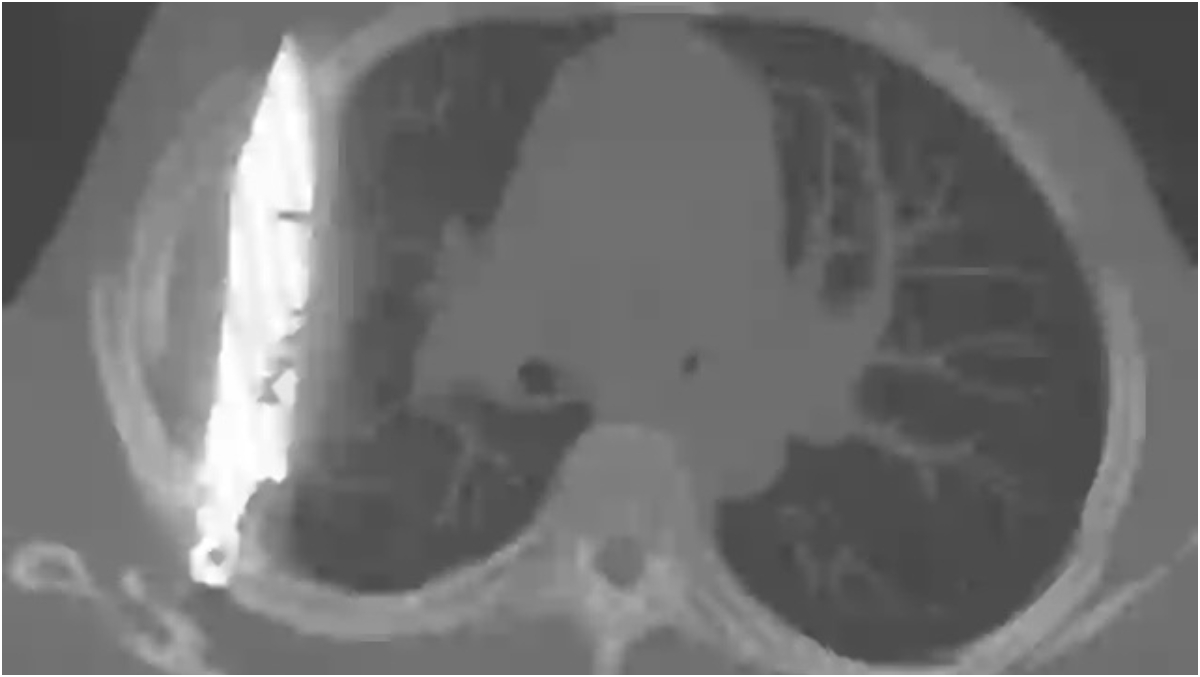

Radiografia a dezvăluit că bărbatul avea un cuțit de dimensiuni considerabile înfipt adânc în piept!

După ce au solicitat o radiografie, a fost găsit un „obiect metalic” imersat, iar medicii și-au dat seama că este o lamă lungă de cuțit, înconjurată de „puroi și țesut necrotic”.

În urma discuțiilor cu pacientul, s-a aflat că acesta fusese înjunghiat în urmă cu 8 ani, iar lama metalică intrase în corp prin umărul drept.